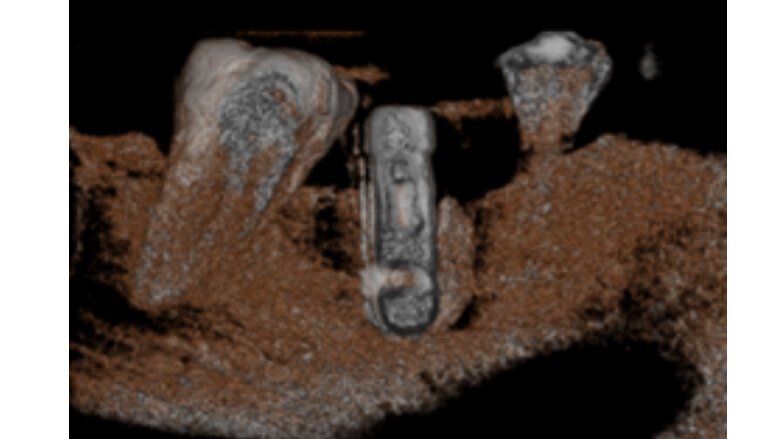

En las imágenes tomográficas (Figuras 2,3) se observa una zona hipodensa en la parte distal del implante, que tiene un halo alrededor del mismo. A los 15 meses, esta imagen hipodensa había desaparecido (Figuras 4,5,6).

Fig 7. Imagen de reconstrucción del volumen donde se puede observar aumento de la densidad ósea en distal y mesial del implante.

La evidencia presentada de este caso indica que para la evaluación de la peri-implantitis no solo se debe realizar un examen clínico con radiografías periapicales, sino un estudio con Tomografía Cone Beam, ya que esta ayuda diagnóstica nos muestra el detalle de lo que está sucediendo con la parte ósea y en el implante. No utilizar esta herramienta CBCT para evaluar la situación clínica nos puede llevar a un mal diagnóstico y por ende a un mal procedimiento, poniendo en riesgo tanto a paciente como a implante.

De hecho, la tomografía CBCT nos permite ver más allá de lo visible y conocer, por el volumen y características de la imagen adquirida, una información altamente específica que hasta hace poco era imposible de inferir.